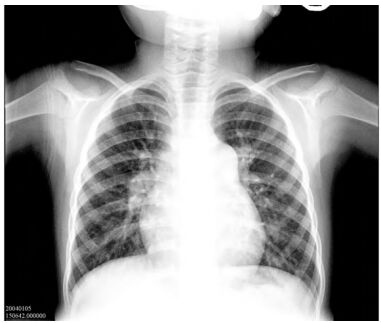

87 3 歲女童,最近半年容易疲倦,上樓梯容易呼吸喘及胸痛。身體診察無明顯發紺,第二心音變大聲, 心電圖檢查顯示有右心肥厚(right ventricular hypertrophy),胸部 X 光如圖所示。其最可能患有何種心臟病?

(A)完全大動脈轉位(d-transposition of great arteries) (B)肺動脈高壓症(pulmonary arterial hypertension) (C)法洛氏四重症(tetralogy of Fallot) (D)肺動脈瓣狹窄(pulmonary valve stenosis)